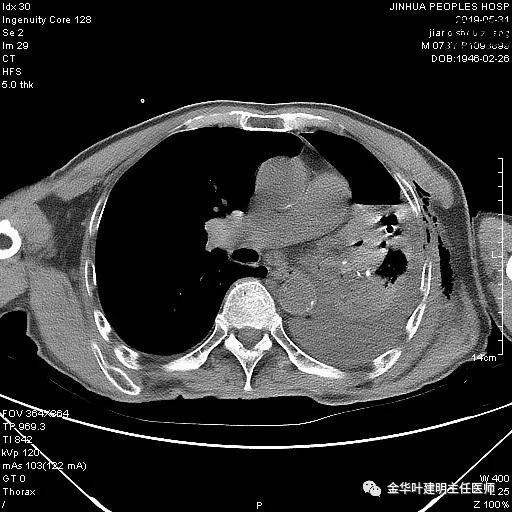

6.4上午:24小时引流出血性乳糜液1800毫升。是否再次手术进行右进胸胸导管结扎,抑或继续保守治疗非常纠结!压力非常大!!多方讨论会诊无法取得一致意见,但一般认为,引流量在1000毫升以上宜积极手术。情况与浙二医院范军强教授联系,请求指导,范教授认为左侧肺手术,损伤胸导管主干的机会较小,多数可保守治疗而愈。在他们的病例中,也有结扎胸导管后引流量仍无减少,效果并不能完全保证。建议可以考虑胸管夹管观察(因为淋巴管压力低,予以适当的压力,漏出量可能会明显减少),同时继续禁食,并静脉营养支持,引流管口可能会有渗液,注意更换敷料。与家属充分沟通后决定试夹管;这天血色素9.0 g/L;胸部CT复查示:

夹管情况下,于6.5复查胸片:

感觉左肺密度还可以,肺没有被全部压萎陷,积液有,但不是特别多。